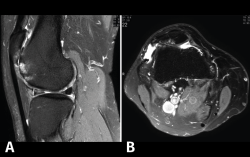

4.2. Infartos

Los infartos medulares óseos aparecen en el 0,06% de los pacientes a quienes se les ha realizado una RM del aparato locomotor. Se presentan como lesiones segmentarias, puramente medulares, sin afección cortical, normalmente múltiples y que afectan predominantemente a los huesos largos de las extremidades, sobre todo las inferiores. La RM es esencial en el diagnóstico por imagen, apareciendo como lesiones óseas intramedulares de contornos serpiginosos hipo- o isointensos en secuencias T1 e hiperintensos en T2. Por tanto, la RM es el instrumento crucial en las fases iniciales, ya que permite caracterizar las lesiones y proceder a su diagnóstico temprano(19)(Figura 52).

Figura 52. A: corte de secuencia coronal T2 Fat-Sat con infartos óseos en el fémur y la tibia; B: corte de secuencia sagital T1 con infartos óseos en el fémur y la tibia.